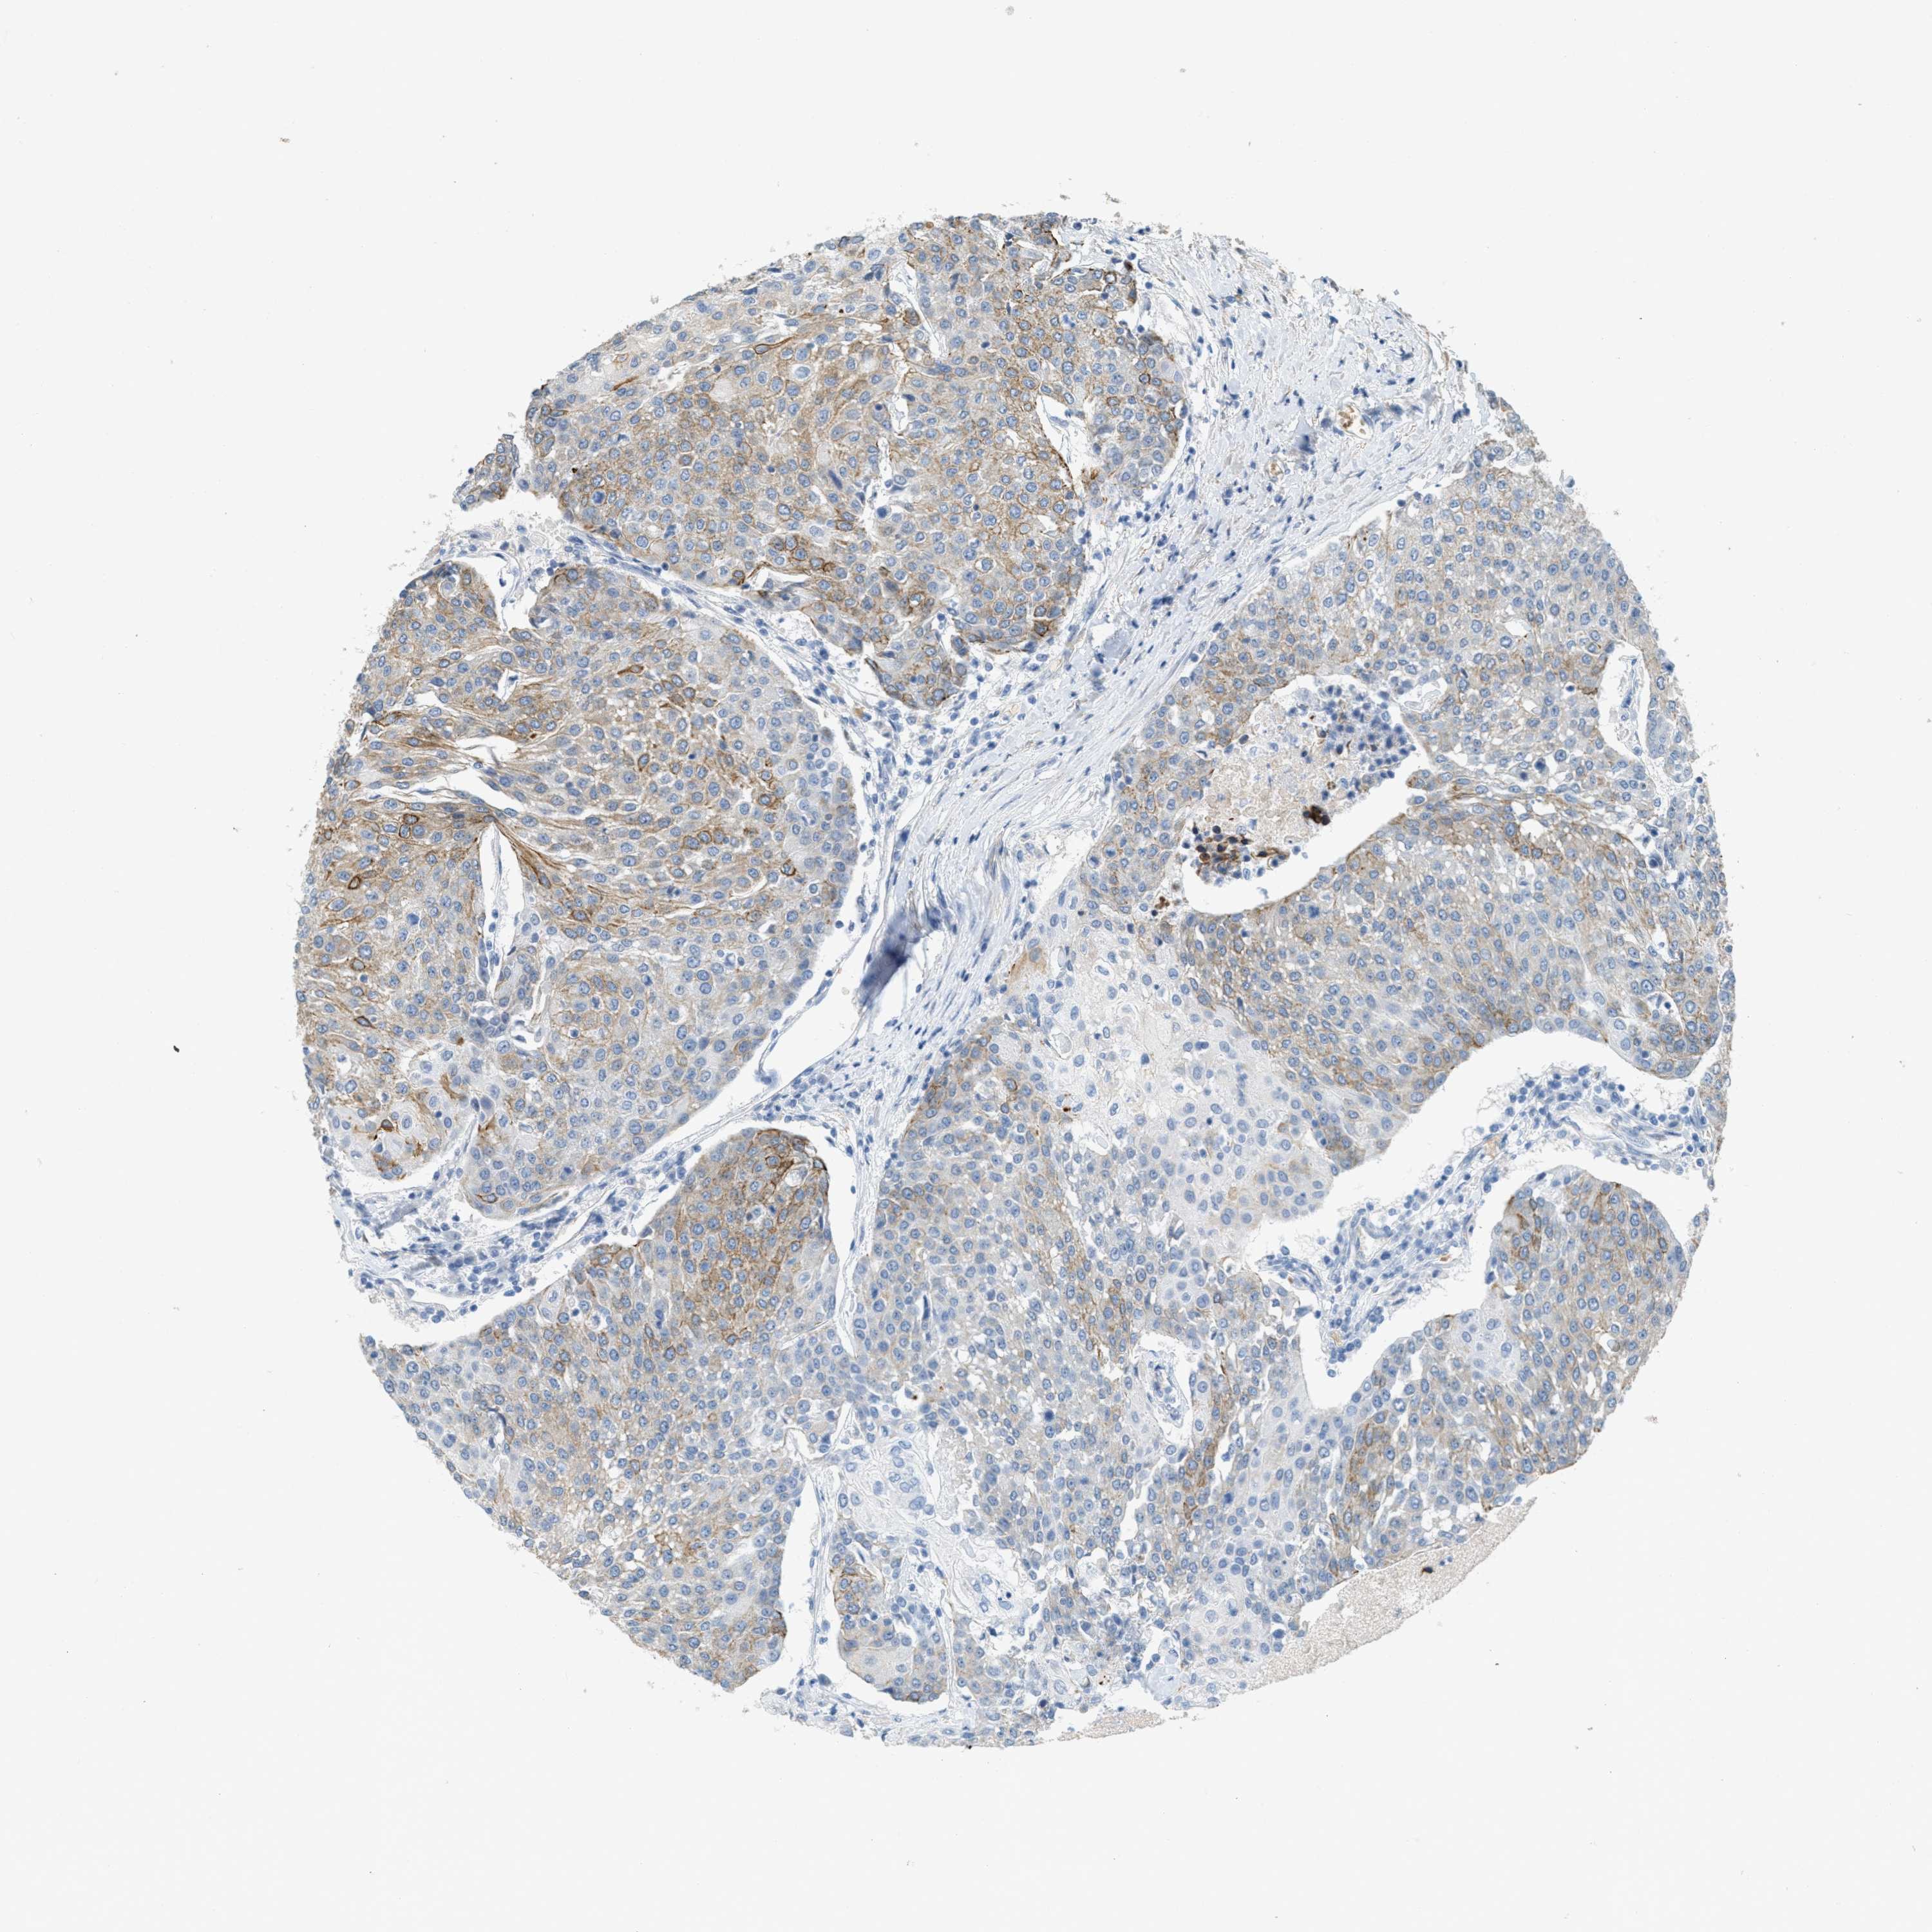

UROTHELIAL CANCER - Protein expressioni

A mouse-over function shows sample information and annotation data. Click on an image to view it in a full screen mode. Samples can be filtered based on level of antibody staining by selecting one or several of the following categories: high, medium, low and not detected. The assay and annotation is described here.

Note that samples used for immunohistochemistry by the Human Protein Atlas do not correspond to samples in the TCGA dataset.

Antibody stainingi

Antibody staining in the annotated cell types in the current human tissue is reported as not detected, low, medium, or high, based on conventional immunohistochemistry profiling in selected tissues. This score is based on the combination of the staining intensity and fraction of stained cells.

Each image is clickable and will lead to virtual microscopy that enables deeper exploration of all samples and also displays staining intensity scores, fraction scores and subcellular localization as well as patient and tissue information for each sample.

Antibody HPA017642

Staining

High

Medium

Low

Not detected

Intensity

Strong

Moderate

Weak

Negative

Quantity

>75%

75%-25%

<25%

None

Location

Nuclear

Cytoplasmic/membranous

Cytoplasmic/membranous,nuclear

Urothelial carcinoma, Low grade

Urothelial carcinoma, High grade